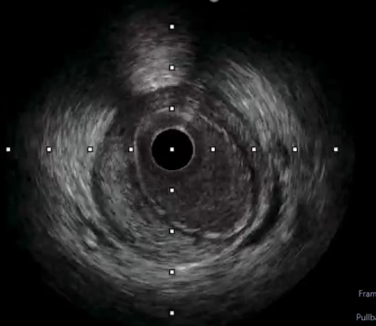

PCI began by engaging a 7Fr JR 4.0 to the RCA ostium via right femoral artery. Wiring initially performed with Runthrough NS through Fine Cross microcatheter, but wire entered subintimal space. Several manipulations to reposition the wire were unsuccessful. Immediate contrast injection showed no flow to the distal part due to abrupt closure of the RCA Patient became angina with marked ST-segment elevation. Rewiring was immediately attempted using Fielder XT-A through Fine Cross microcatheter and the wire successfully entered true lumen A 1.5 x 1.5 mm NC balloon was placed at the lesion but balloon ruptured.A 2.0 x 15 mm NC balloon with extension catheter as support but balloon ruptured.Finally A 2.0 x 20 mm NC scoring balloon successfully inflated then flow was restored with TIMI III flow.Angina relieved, ST-segment lower and hemodynamic improvedIVUS showed massive-compressive intra mural hematoma along distal to proximal RCA with intimal tear of dissection, and the wire within false lumen at mid part RCA.Coronary fenestration attempted using 3.0 x 15 mm NC scoring balloon inflation with dual guidewire inside the lumen.Hematoma surprisingly propagated marked by contrast trapping and no flow to PLBFenestration performed again using 2.5 x 15 mm NC scoring balloon and flow successfully restored.Four DES finally decided to be deployed at distal to ostial RCAFinal angiogram showed excellent result with TIMI III flow, hematoma was disappeared with good stent apposition on IVUS examination